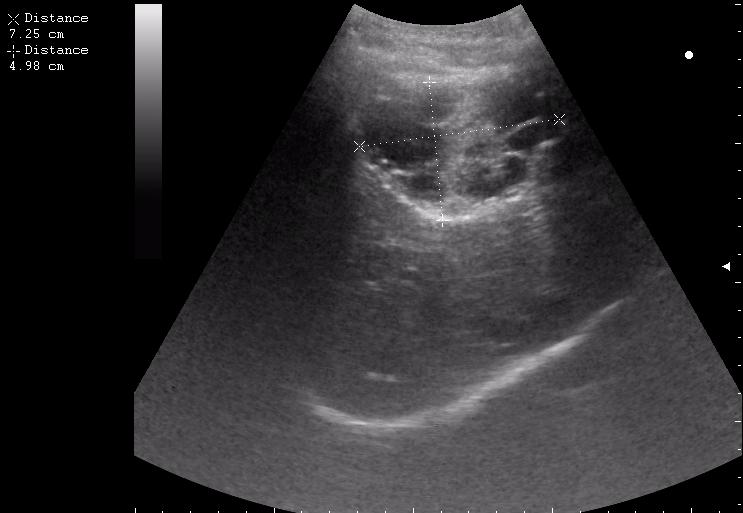

17-летняя девушка с множественными поражениями печени

абсцесс передней брюшной стенки (через 2 недели п.о.)